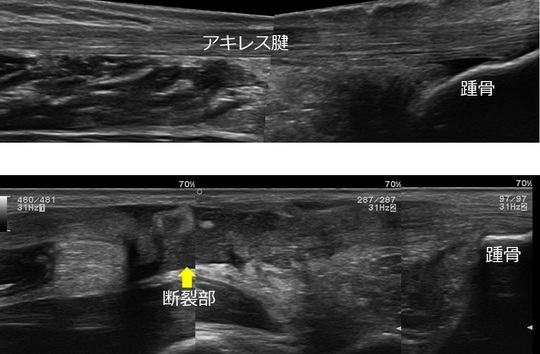

エコー画像(上:正常 下:断裂画像)

左:患側 右:健側 アキレス腱が陥凹している